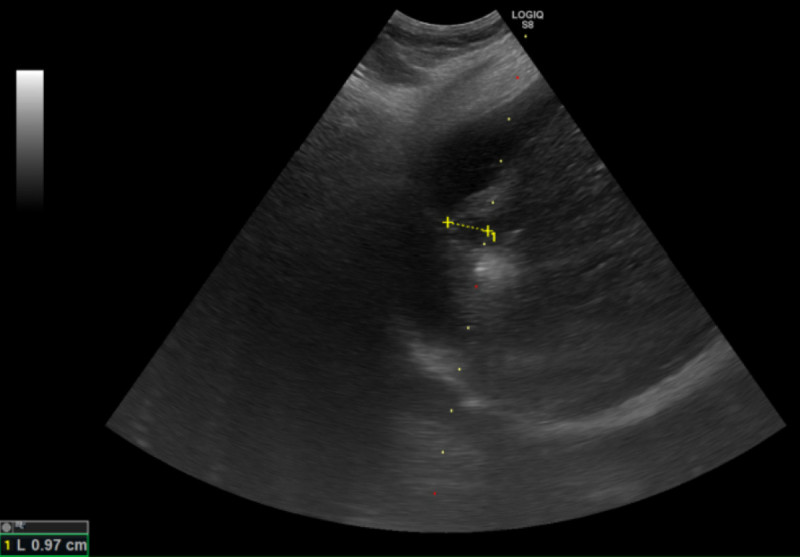

鄭煜明解釋,電燒治療是透過超音波導引定位,使用電極產生電流,造成離子震動產生超過60度的熱能氣化腫瘤,比起手術能更完整保留健康的肝臟組織,肝癌患者平均5年的復發率高達7成,因此電燒治療對於可能復發,需要多次治療的患者而言更具優勢,且此療法住院時間短,通常3日左右即可出院。